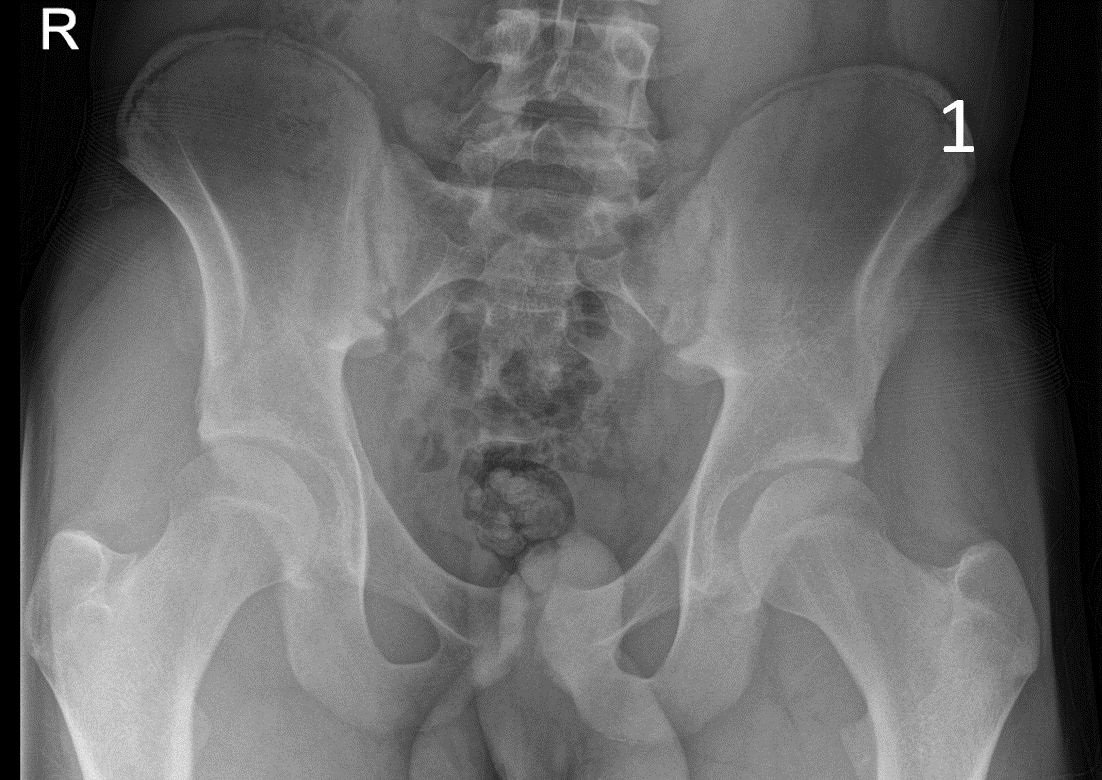

A 17-year-old male presented with severe pain in his right groin. He felt a ‘pop’ in his right groin whilst sprinting and was struggling to weight-bear. A radiograph excluded any bony abnormality (Figure 1) and an ultrasound scan showed no evidence of inguinal or femoral hernia.

The patient was focally tender in the right iliac fossa at the level of the anterior superior iliac spine (ASIS). At this site, there was muscle fibre disruption and a haematoma at the insertion of the sartorius tendon with minimal retraction (Figure 2). There was cortical irregularity at the ASIS and a bony fragment within the retracted tendon and also neovascularisation here on power Doppler (Figure 3). On comparison to the contralateral side, there was altered architecture of the sartorius muscle with a clear defect while the left side looked normal (Image 4). Ultrasound appearances in keeping with a sartorius tendon avulsion. This was treated conservatively with rest, analgesia and a return to normal activities after two months. Surgical interventions are uncommon and are reserved for when the fracture fragment has migrated more than 3cm.

This injury is associated with young athletes plus young rugby and football players.